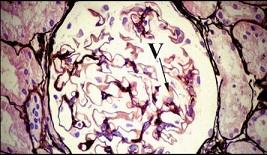

问题 从此病理图片(PASM染色)可见GBM空泡变性(Ⅴ),考虑为 ( )

选项 A.微小病变 B.Ⅰ期膜性肾病 C.Ⅱ期膜性肾病 D.Ⅲ期膜性肾病 E.Ⅳ期膜性肾病

答案 B